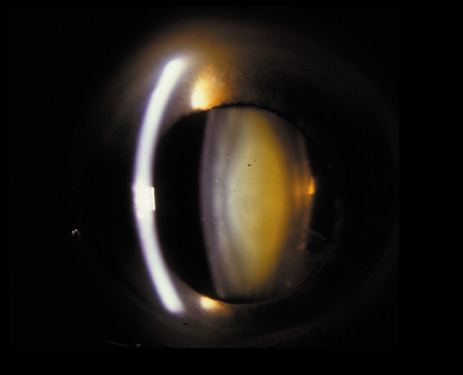

Nuclear cataracts tend to progress slowly. The refractive index of the lens changes as the nucleus progressively hardens, which usually results in increasing myopia.20,21 In some patients this is accompanied by optical distortion, especially of distant images, while near vision remains unaffected. A nuclear cataract is best seen with the narrow-beam direct illumination employed by the slit-lamp, which reveals the color and generalized haze or opalescence of the nucleus. In the early stages, the two halves (cotyledons) of the embryonic nucleus remain visible (Fig. 3). Later the entire nucleus appears as a homogeneous mass in contrast to the cortex (Fig. 4). Retroillumination may show the “oil droplet” effect (Fig. 5). Sometimes one may notice crystals in the lens nucleus (known as a Christmas tree cataract; Fig. 6A and B).

Fig. 4. Advanced nuclear cataract. Note the homogeneous nuclear opacity.

Fig. 5. “Oil droplet” appearance of a pure nuclear cataract seen on retroillumination examination.